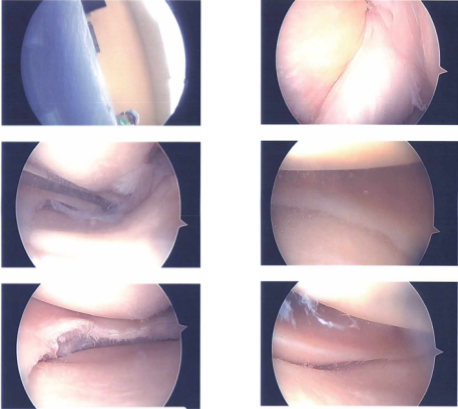

A lateral parapatellar incision was used to create an entry portal, through which an arthroscope was introduced. The patella and trochlea both had grade 1 to grade 2 osteoarthritic alterations upon examination of the patellofemoral compartment.

The posterior horn of the medial meniscus was torn, as evidenced by a medial tibiofemoral compartment examination. Spinal needle and blade were used to create a medial entrance hole. A shaver was used, together with biters and shaver, to clean the damaged meniscus.

Along the body of the posterior horn of the medial meniscus, a balanced margin was attained. Intact was the root. The medial tibiofemoral compartment’s cartilage was undamaged.

The intercondylar notch examination revealed an undamaged ACL. Meniscus and cartilage that were examined in the lateral tibiofemoral compartment were in good condition. Once more, a shaver was used to tease grade 1 to grade 2 osteoarthritic alterations in the patellofemoral compartment. Final images were captured and stored.

Intraoperative Images